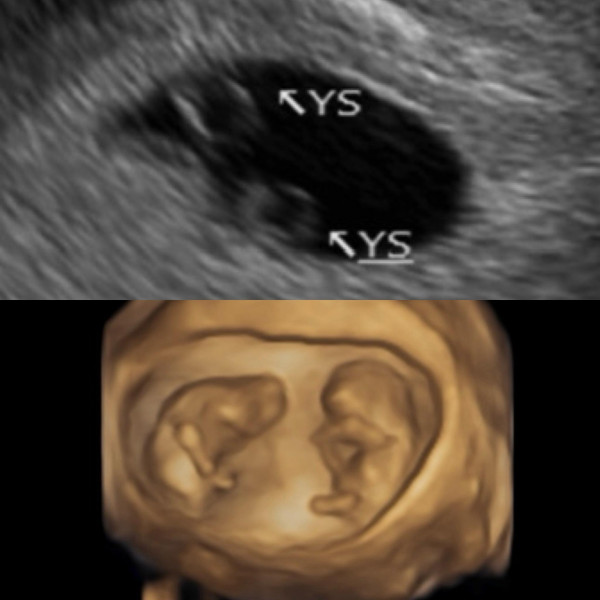

最近,鄭家純在社交平台上報喜,貼出珍貴的超聲波照片,並寫著:「阿純目前懷孕12週,是同卵雙胞胎。」她透露,在經歷小產痛楚後,醫生曾建議她先休養,相隔3個月後才開始嘗試自然懷孕,因此她乖乖避孕。沒想到幸運之神悄悄降臨,她在小產後月經還沒來的時候就意外懷孕!在過年除夕當日,她發現驗孕棒上出現淡淡的兩條線。其後經過在東京與台灣兩地的詳細產檢,終於確認懷孕的喜訊,而且今次更是難得的同卵雙胞胎! 鄭家純感性分享第一次聽到雙胞胎心跳聲的震撼時刻:「我在6週就聽到心跳,聽到的瞬間眼淚就掉下來,因為上次沒有聽到。」